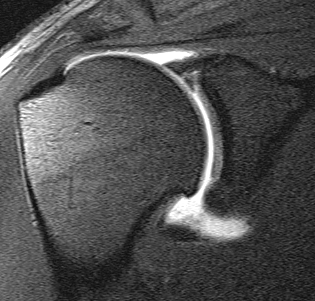

MRI

Supralabral ganglion cyst

- associated with posterior SLAP tears